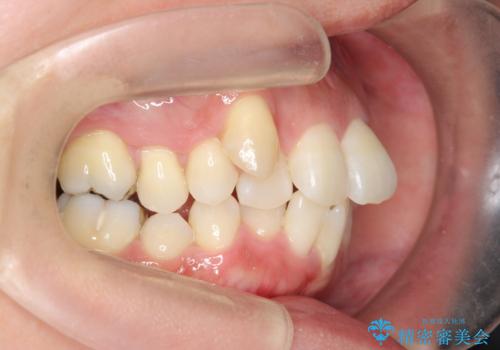

通常は八重歯の抜去は行わず、小臼歯の抜去を行いワイヤー矯正を行いますが、八重歯を抜去することでマウスピースで現実的に達成できる機能的な歯並びを獲得できるよう治療計画を立案します。

治療に制約がある場合でも、現実的な治療ゴールを設定することで機能的・審美的な歯並びを手に入れることができました。